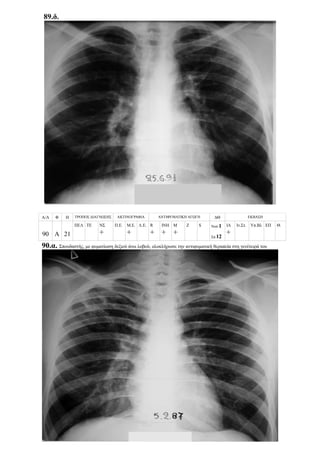

Περίπτωση 21η:

Α/Α Φ Η ΤΡΟΠΟΣ ΔΙΑΓΝΩΣΗΣ ΑΚΤΙΝΟΓΡΑΦΙΑ ΑΝΤΙΦΥΜΑΤΙΚΗ ΑΓΩΓΗ ΔΘ ΕΚΒΑΣΗ

21 Θ 7

ΠΕΛ ΤΕ ΝΣ

+

+ ++ +++

R

ΙΝΗ

Μ

Z S Νοσ.

Σπ.12

ΙΑ

Ιν.Στ. Υπ.Βλ ΕΠ Θ.

21.α.

21.β.

6/9/1996